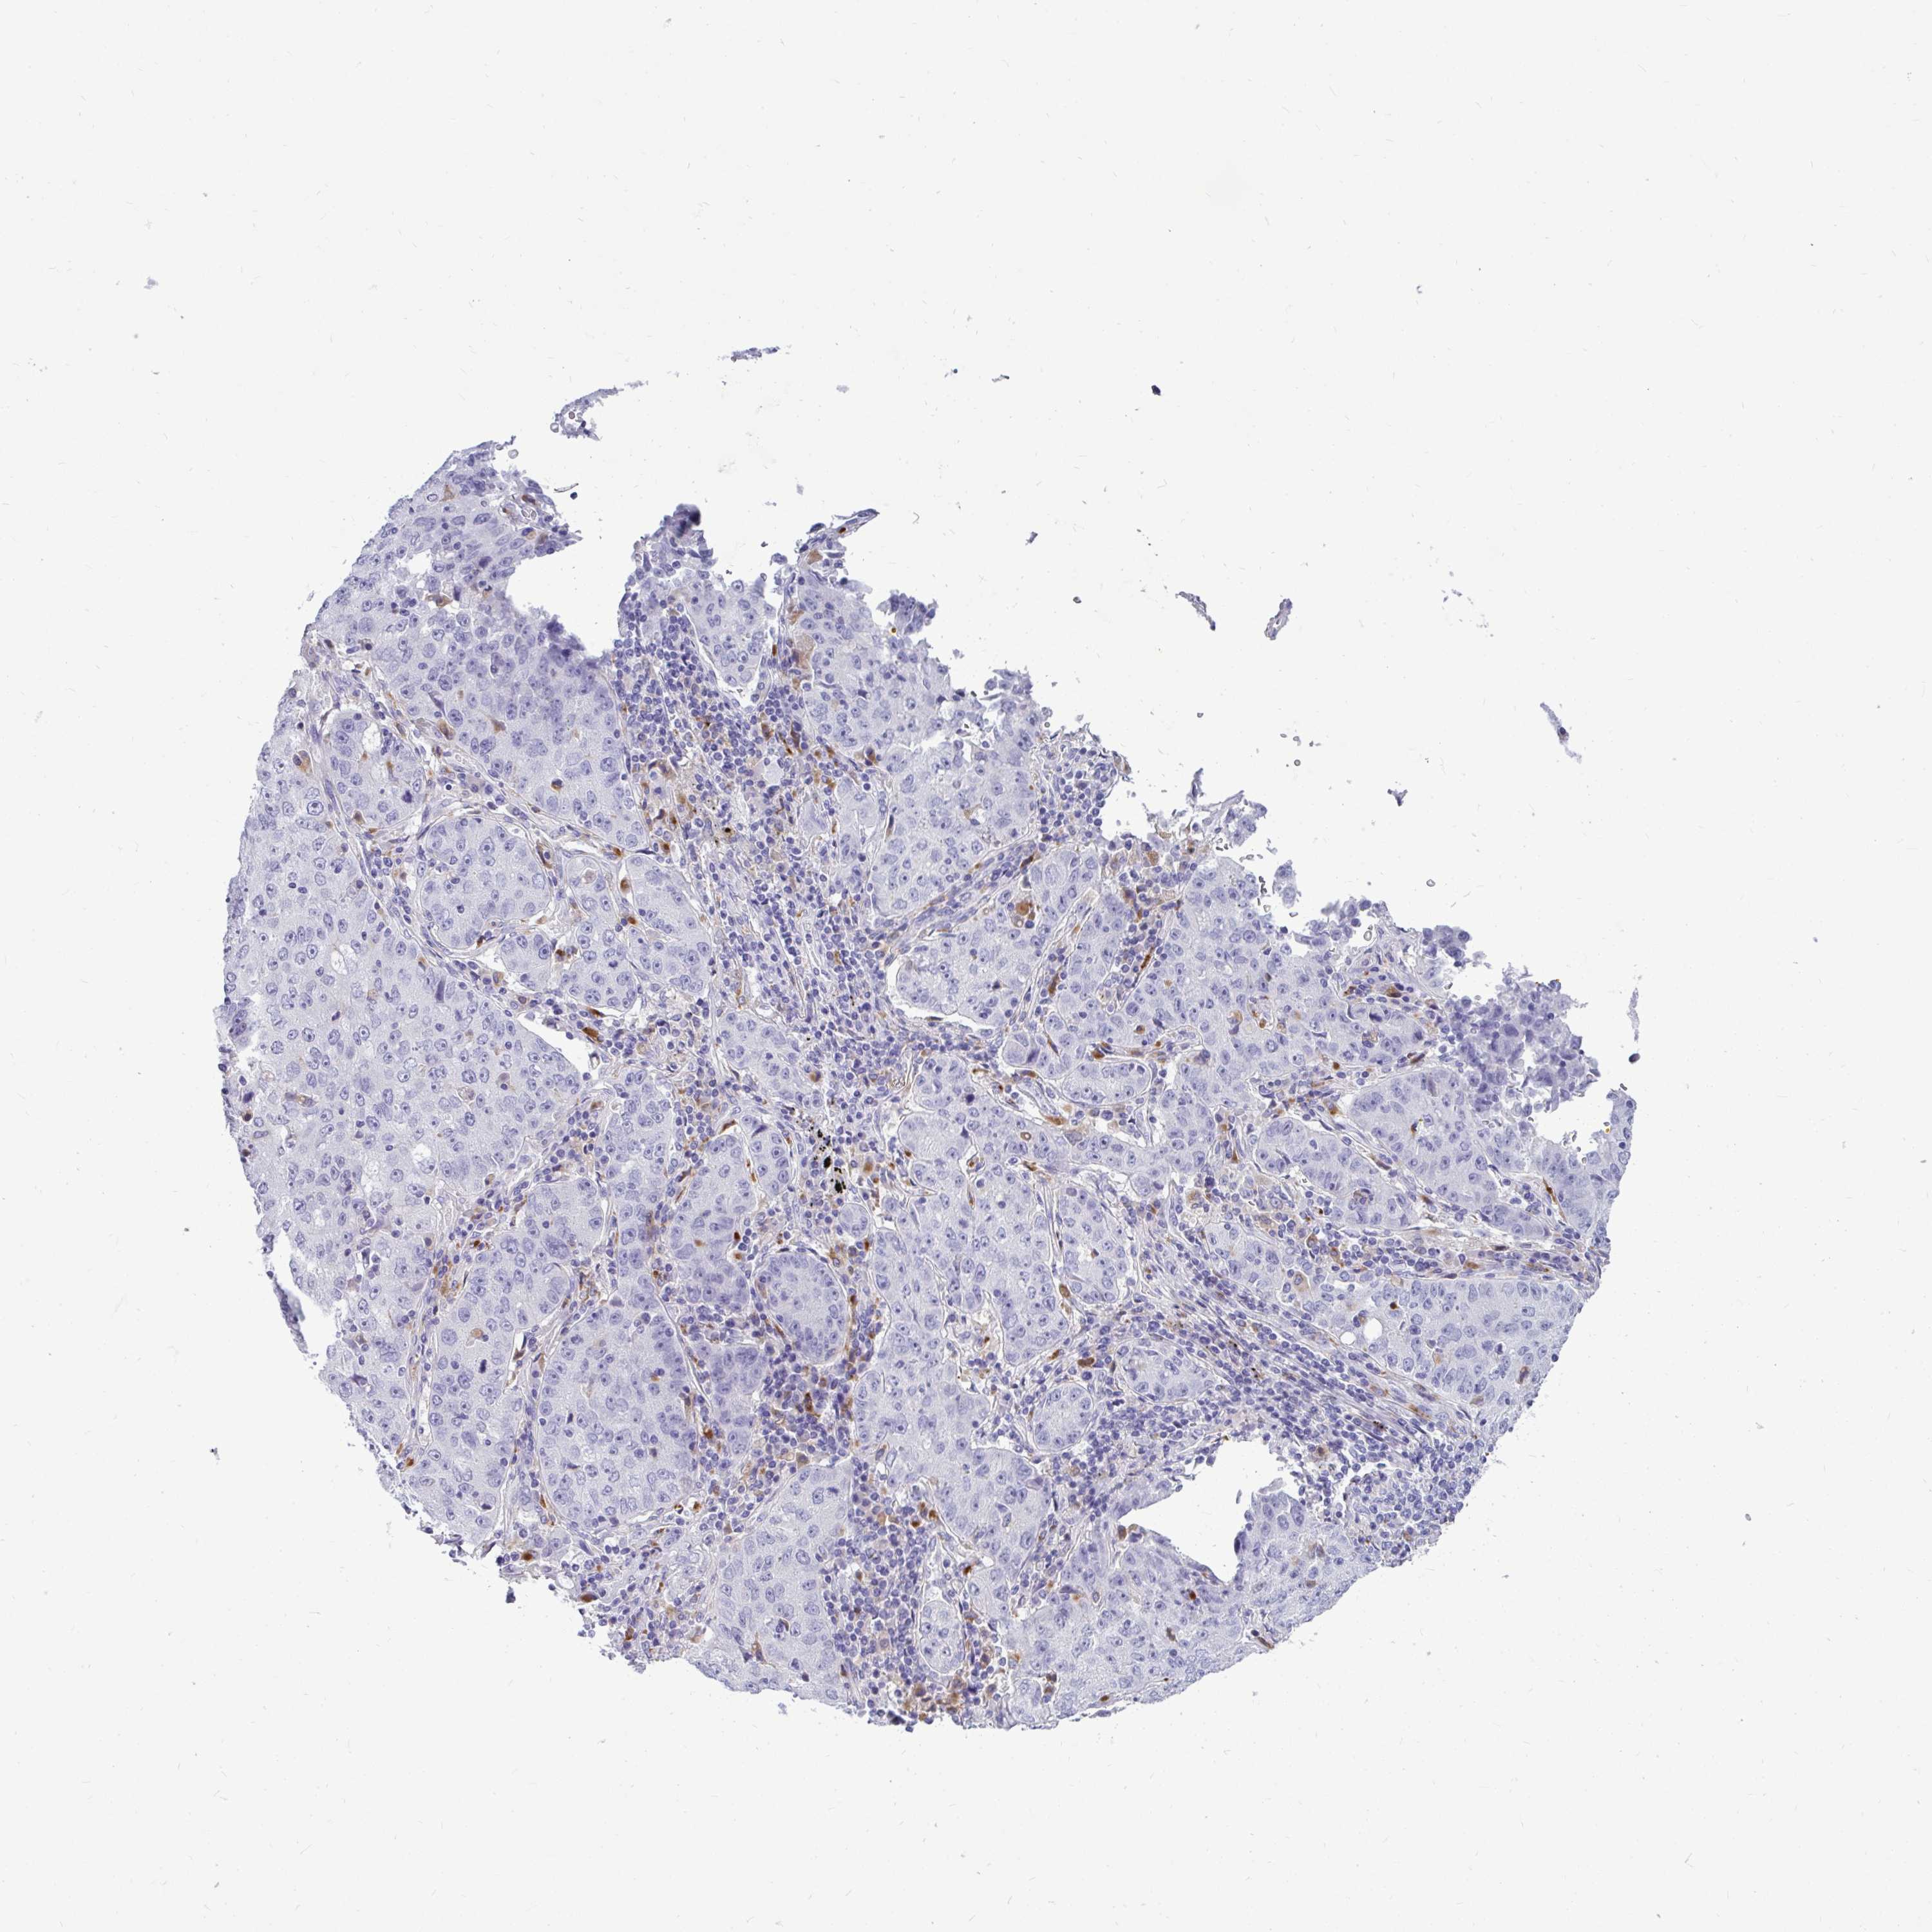

LUNG ADENOCARCINOMA (TCGA) - Interactive survival scatter ploti

The Survival Scatter plot shows the clinical status (i.e. dead or alive) for all individuals in the patient cohort, based on the same data that underlies the corresponding Kaplan-Meier plots. Patients that are alive at last time for follow-up are shown in blue and patients who have died during the study are shown in red.

The x-axis shows the expression levels (FPKM) of the investigated gene in the tumor tissue at the time of diagnosis. The y-axis shows the follow-up time after diagnosis (years). Both axes are complimented with kernel density curves demonstrating the data density over the axes. The top density plot shows the expression levels (FPKM) distribution among dead (red) and alive patients (blue). The right density plot shows the data density of the survived years of dead patients with high and low expression levels respectively, stratified using the cutoff indicated by the vertical dashed line through the Survival Scatter plot. This cutoff is automatically defined based on the FPKM cutoff that minimizes the p-score. The cutoff can be changed by dragging the vertical line or by entering a cutoff value in the square labeled "Current cut-off".

Under the Survival Scatter plot the p-score landscape (black curve; left axis) is shown together with dead median separation (red curve; right axis). Dead median separation is the difference in median mRNA expression between patients who have died with high and low expression, respectively. It is calculated as follows: median FPKM expression of dead patients with high expression - median FPKM expression of dead patients with low expression. This is intended to aid the user in visually exploring custom cutoffs and the associated p-scores and dead median separation.

Individual patient data is displayed and can be filtered by clicking on one or more of the category buttons on the top of the page. Categories describing expression level and patient information include: high, low, alive, dead, female, male and tumor stages. The scale of the x-axis can be toggled between linear and log-scale by clicking on the "x log" button. Mouse-over function shows TCGA ID, patient information and mRNA expression (FPKM) for each patient.

& Survival analysisi

Kaplan-Meier plots summarize results from analysis of correlation between mRNA expression level and patient survival. Patients were divided based on level of expression into one of the two groups "low" (under cut off) or "high" (over cut off). X-axis shows time for survival (years) and y-axis shows the probability of survival, where 1.0 corresponds to 100 percent.

CTSZ is not prognostic in Lung Adenocarcinoma (TCGA)

: 164.13

Average pTPM 286.3

Number of samples 497